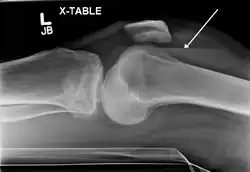

In all injuries to the tibial plateau radiographs (commonly called x-rays) are imperative. Computed tomography scans are not always necessary but are sometimes critical for evaluating degree of fracture and determining a treatment plan that would not be possible with plain radiographs.[10] Magnetic Resonance images are the diagnostic modality of choice when meniscal, ligamentous and soft tissue injuries are suspected.[11][12] CT angiography should be considered if there is alteration of the distal pulses or concern about arterial injury.

Lipohemarthrosis (presence of fat and blood from bone marrow in the joint space after an intraarticular fracture) seen on X-ray in a person with a subtle tibial plateau fracture -

Lipohemarthrosis due to a tibial plateau fracture -